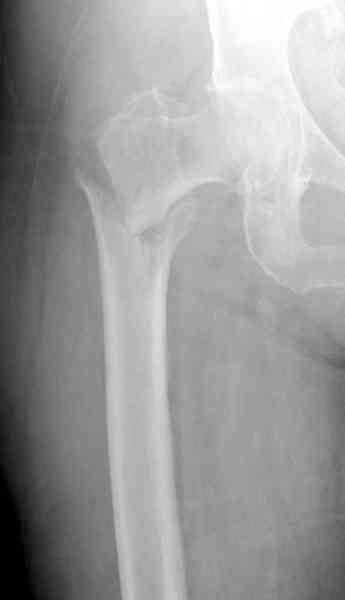

Мы получили испытательный вариант инструментария для пробы, хотя компания объявила, но ещё не для широкой публики, обещают к сентябрю. За полтора месяца, включая сегодняшнюю, вот уже восьмая операция по счету. Удобный инструментарий, ничего лишнего, научились делать быстро, посмотрим что будет, пока нравится.

Все больные пожилого возраста, первые уже успели появиться на амбулаторном приеме, пока без осложнений.

Здесь сканнированные снимки импланта и операционные снимки больной.

На этом снимке процесс компрессии нижним болтом.

Итог